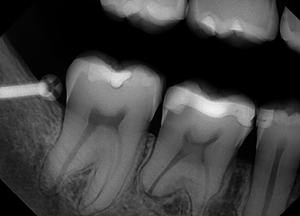

An example of a good X-ray image